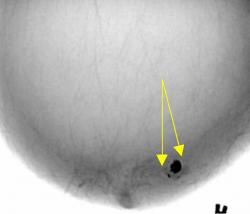

Протокол исследования. Общий фон инволютивно измененной молочной железы (в годы климакса). В правой молочной железе в передних отделах, в верхнем наружном квадранте определяется «узловое образование» значительной интенсивности, однородной структуры (1), неправильно округлой формы, с неровными, местами волнистыми контурами. В окружающей ткани определяются несколько различных размеров очаговых теней значительной плотности. Описанные тени располагаются на фоне локального снижения прозрачности молочной железы (стрелки) – по всей видимости - участок нежного склероза (1 – прямая проекция, 2 – боковая проекция). 3, 4, 5 – патологический участок железы выделен «навигатором», проведена цифровая обработка изображения – тень неоднородной структуры с преимущественным обызвествлением по периферии и известковыми включениями в центре.

Заключение: Инволютивная молочная железы в годы климакса. Фиброаденома (обызвествленная) правой молочной железы с более мелкими обызвествленными фиброаденомами вокруг.